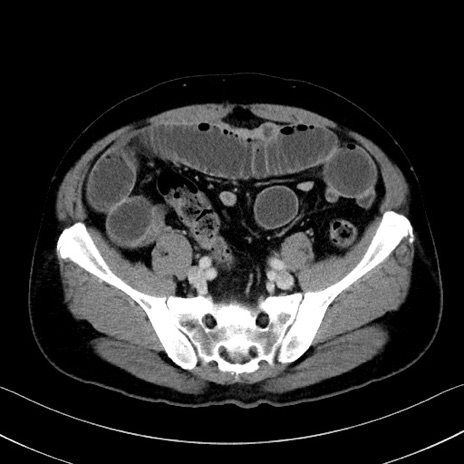

症例35(横断像)

【症例】70歳代 男性

【主訴】腹部膨満、嘔吐

【現病歴】昨日より腹部膨満感出現。本日増悪し、仙痛出現。嘔吐あり、受診。

【既往歴】糖尿病、胆摘後

【身体所見】BP 149/80mmHg、HR 74/min、BT 35.9℃、腹部:膨満、軟、圧痛なし。腸雑音減弱あり。上腹部正中切開瘢痕あり。

【データ】WBC 13500、CRP 1.72

冠状断像